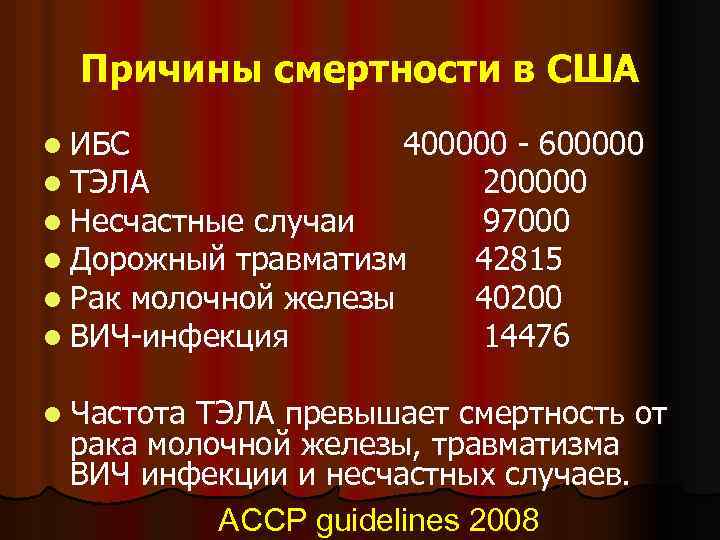

Причины смертности в США l ИБС 400000 - 600000 l ТЭЛА 200000 l Несчастные случаи 97000 l Дорожный травматизм 42815 l Рак молочной железы 40200 l ВИЧ-инфекция 14476 l Частота ТЭЛА превышает смертность от рака молочной железы, травматизма ВИЧ инфекции и несчастных случаев. ACCP guidelines 2008